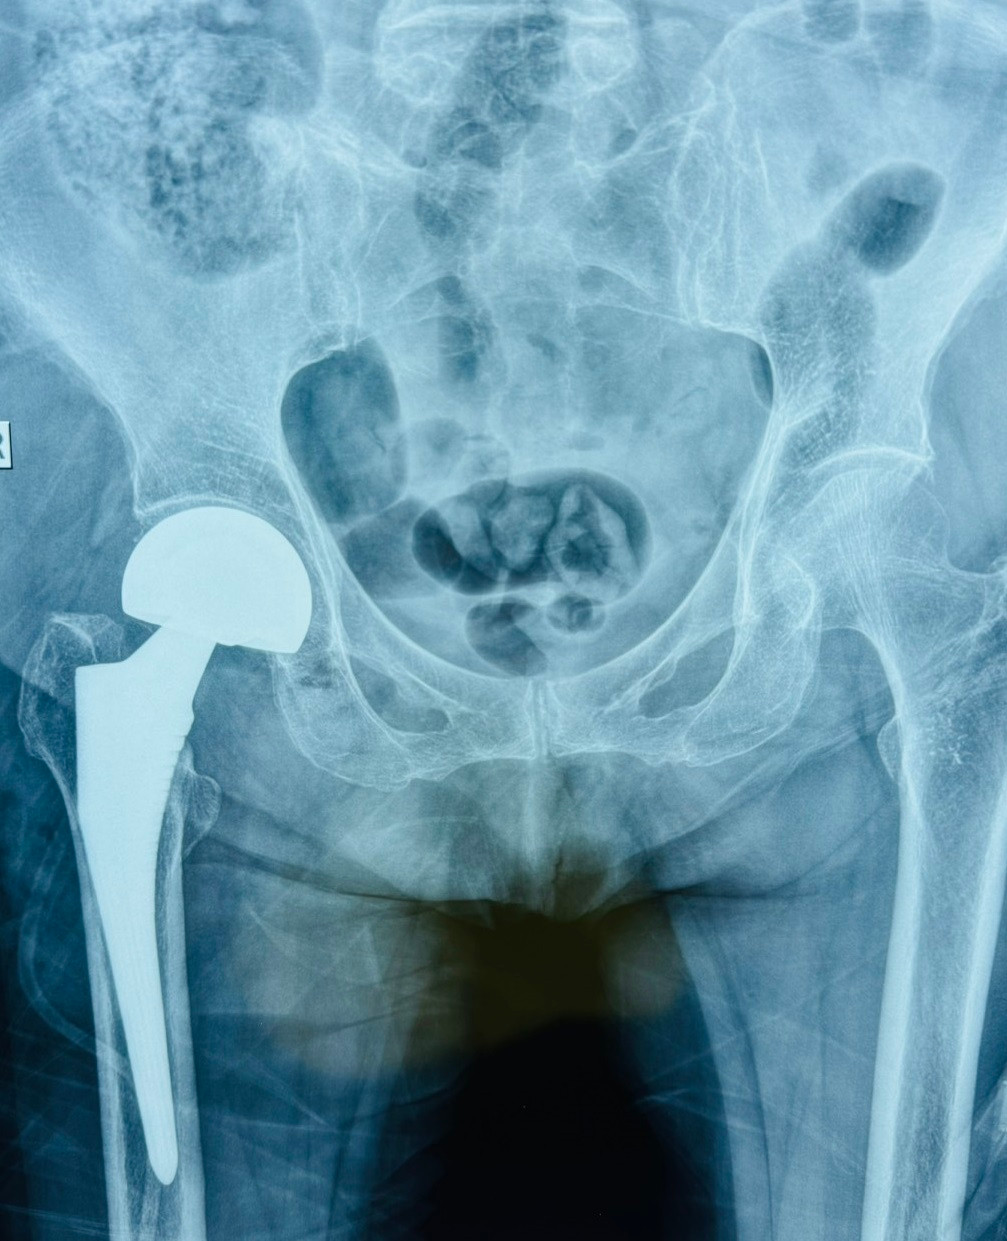

Qua thăm khám và chẩn đoán hình ảnh, bác sĩ phát hiện bệnh nhân bị gãy cổ xương đùi bên phải trên nền cơ địa có nhiều bệnh lý nền. Các bác sĩ đã chỉ định cho bệnh nhân thực hiện cuộc phẫu thuật thay khớp háng bán phần để tránh nguy cơ đối mặt với những biến chứng nguy hiểm sau chấn thương.

Qua kiểm tra hình ảnh, bác sĩ xác định bệnh nhân bị gãy cổ xương đùi bên phải. Để giúp bệnh nhân thoát khỏi tình trạng đau đớn và biến chứng loét tì đè, viêm phổi, viêm đường tiết niệu do nằm một chỗ lâu ngày, các bác sĩ đã chỉ định cho người bệnh thay khớp háng bán phần.

Cả hai trường hợp trên, sau phẫu thuật và tập vật lý trị liệu đã có thể vận động đi lại được. Bác sĩ cho biết, việc thay khớp nhân tạo sẽ giúp người bệnh giảm đau, đi lại được thuận tiện nhất từ đó cải thiện chất lượng cuộc sống.

| Người bệnh lớn tuổi được thay cổ xương đùi bán phần giúp phục hồi vận động |